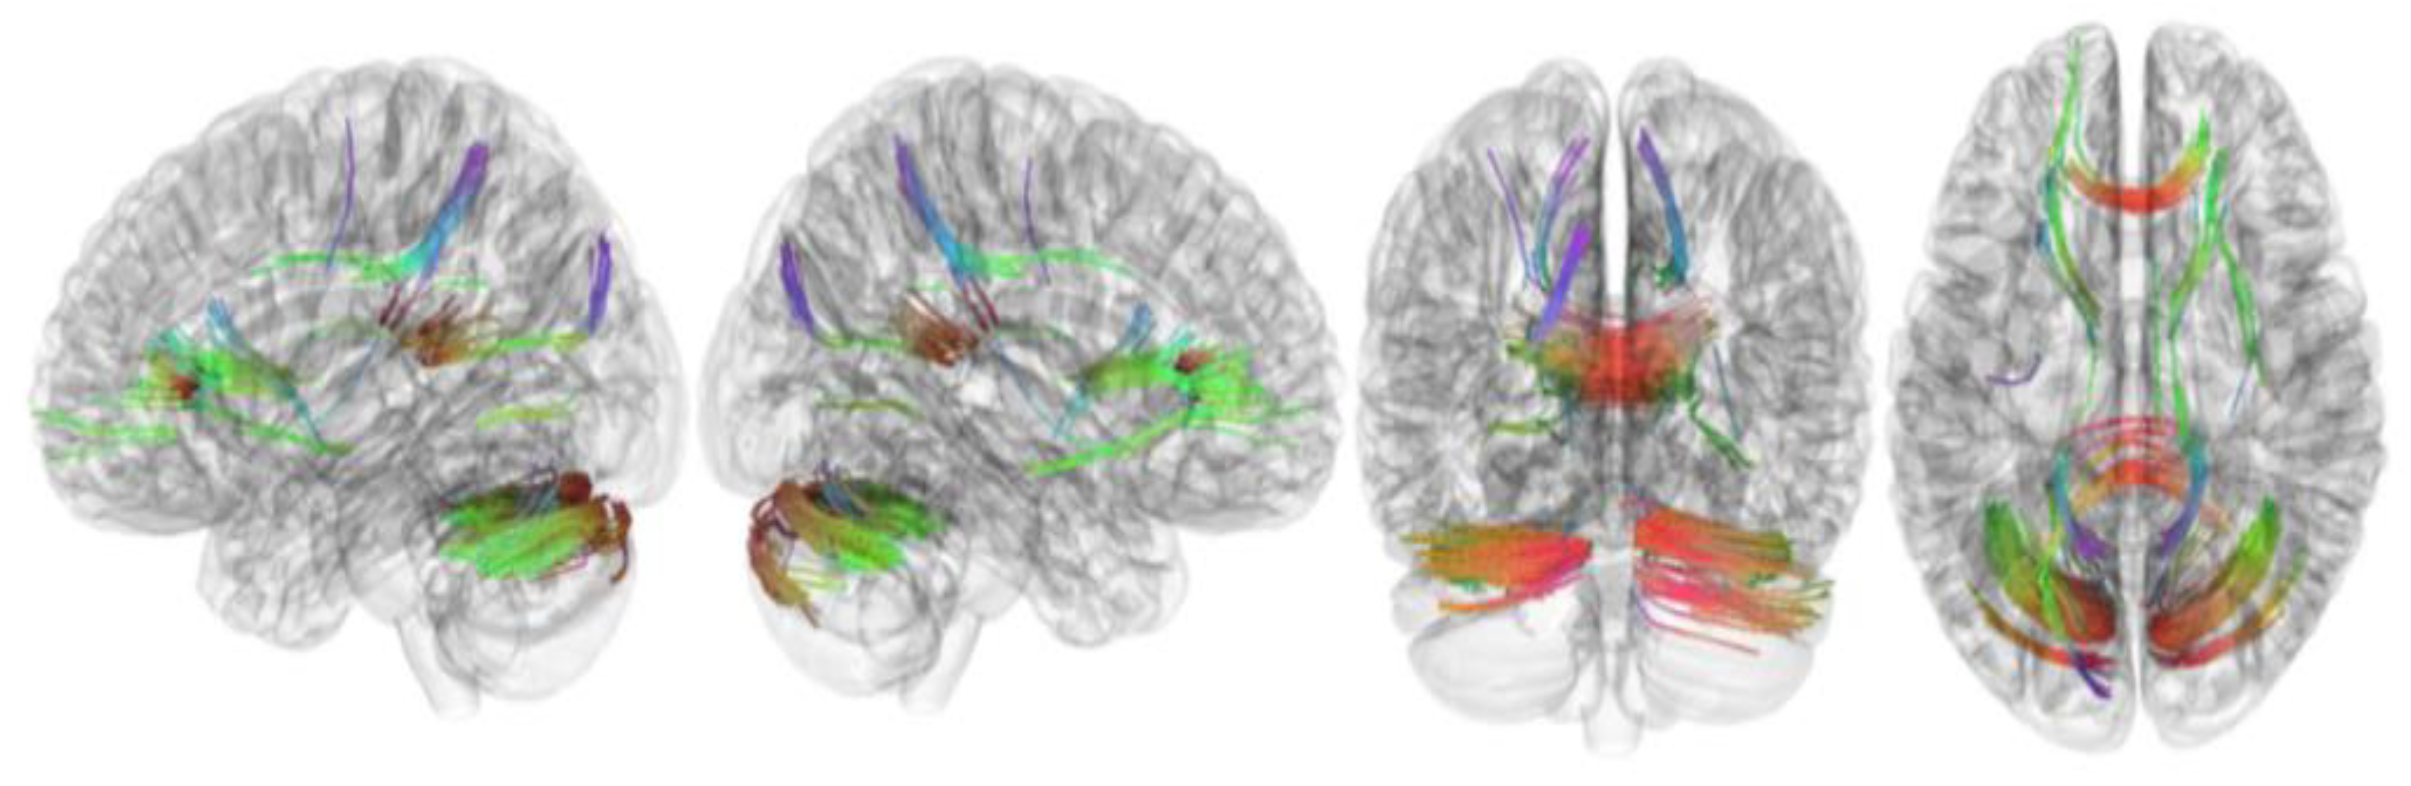

3.2. Tracks with FA Correlated with RLS Severity

| Tracks with positive correlation with RLS severity | Cerebellum, corpus callosum forceps minor, corpus callosum forceps major, corpus callosum body, and cingulum frontoparietal track |

| Tracks with negative correlation with RLS severity | Middle cerebellar peduncle, inferior longitudinal fasciculus, corticospinal tract, corpus callosum forceps minor, cerebellum, frontal aslant tract, dentato-rubrothalamic tract, inferior longitudinal fasciculus, corticostriatal tract superior, and cingulum parahippocampoparietal tract |